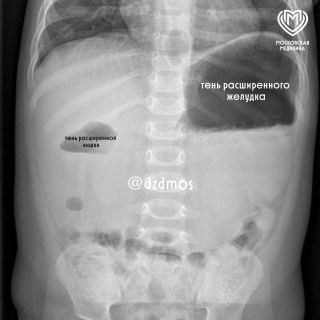

Семимесячную девочку доставили в больницу Сперанского после ежедневных приступов рвоты. Обследование выявило серьёзную проблему: в двенадцатиперстной кишке сформировалась толстая мембрана, почти полностью блокирующая прохождение пищи.